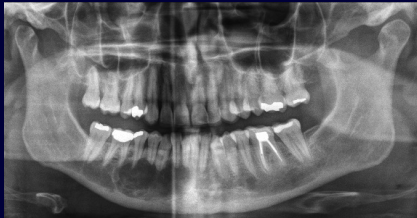

What are the important aspects of assessment for mandibular implants?

1.Mandibular canal 2.Mental foramen 3.Anterior loop of mandibular canal 4.Incisive branch of IAN 5.Lingual canal in the midline